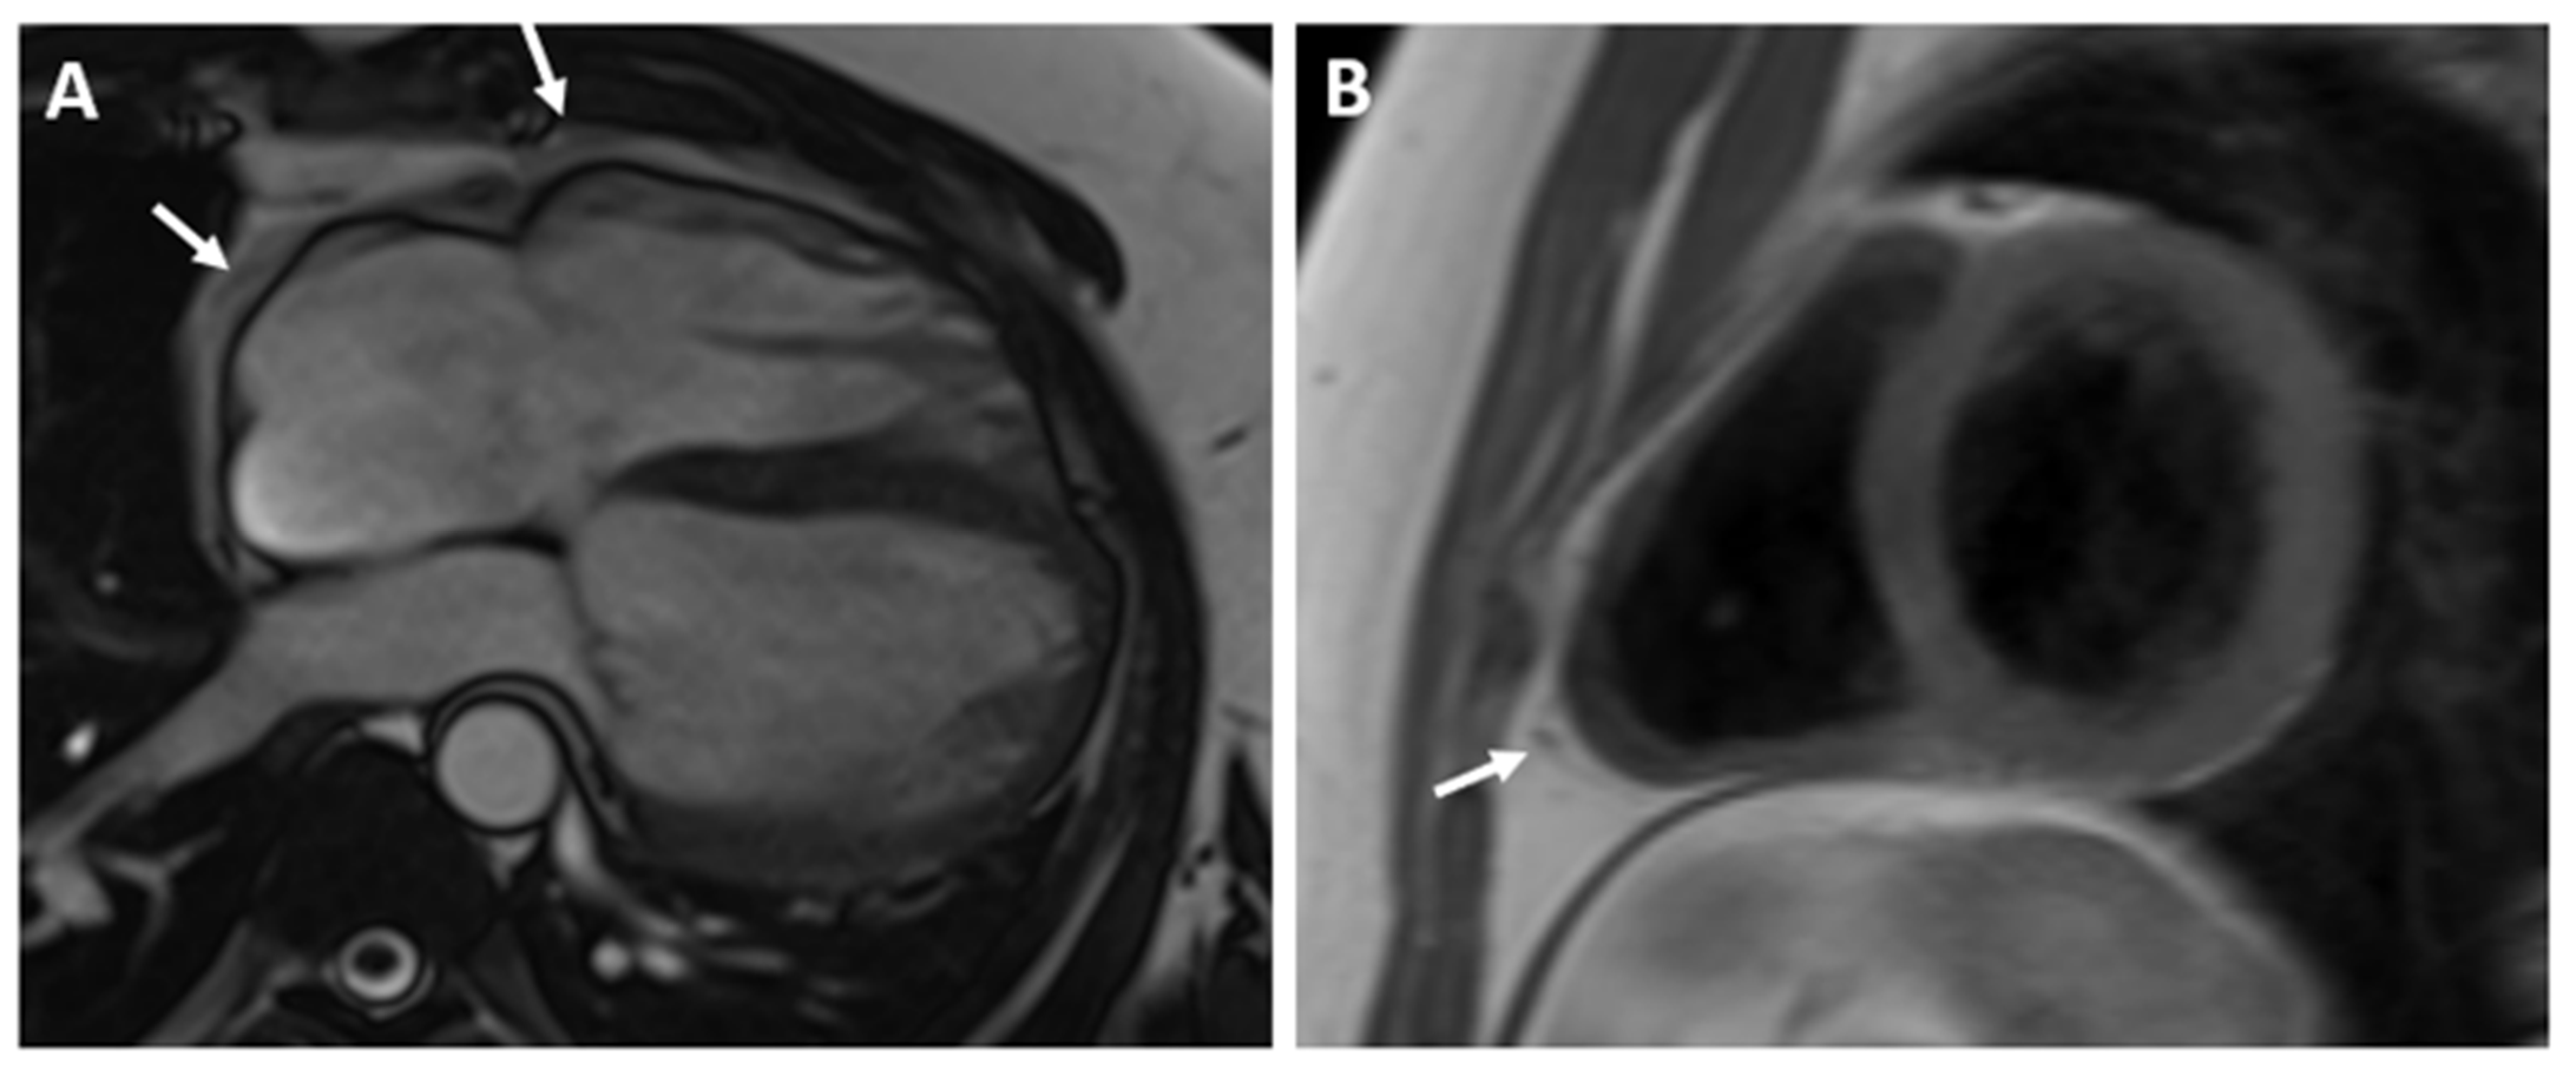

The CMR confirmed the abnormal position of the heart in the left hemithorax with laterally and posteriorly displaced apex and interposition of the lung tissue between the aorta and pulmonary trunk. There was no detectable pericardium overlying the left ventricular wall, and only a small discontinuous segments of pericardium were visualized surrounding the right atrium and right ventricular lateral wall (Figure 3 and Figure 4). Biventricular volumes and function were in the reference range. Additionally, a patent foramen ovale was visualized with no significant left-to-right shunt (Qp/Qs = 1.1).

Figure 3.

(A)—Axial image of the chest shows the displacement of the heart into the left hemithorax with the cardiac apex pointing laterally and posteriorly. (B)—Coronal image of the chest demonstrates the interposition of lung tissue between the aorta and pulmonary artery (white arrow). Ao—aorta; PA—pulmonary artery.

Figure 4.

SSFP CINE image in four chamber view (A) and T1-weighted fast spin-echo in axial view (B) demonstrate discontinuous segments of pericardium surrounding the right atrium and right ventricular lateral wall. No detectable pericardium was found around the left ventricular wall.